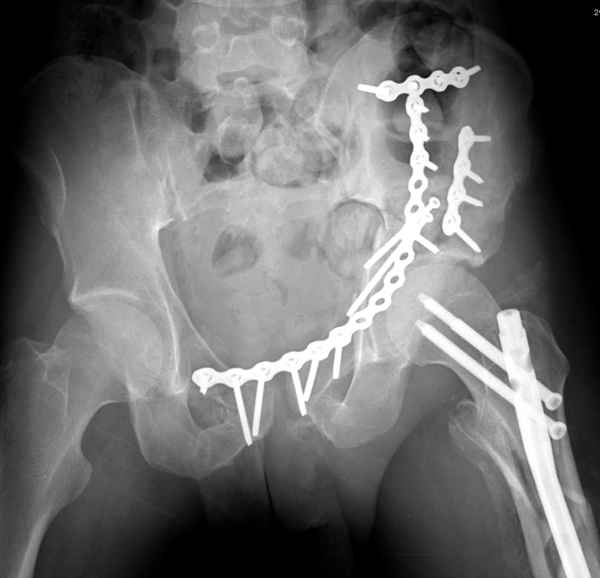

высылаю дополнительно сканы.

Судя по представленным реконструкциям (не очень хорошего качества - много наводок)

мы имеем дело с полупоперечным переломом у которого отломался задний край или его отломали, превратив перелом в полный двухколонный.

По отдельным срезам и тем более по реконструкции трудно судить о сращении крыла и задней колонны с осевым скелетом.

Все выступающие коллеги высказались насчет необходимости стандартных снимков по Judet, потому что для определения тактики лечения переломов вертлужной впадины 3Д снимки малоинформативны.

Из того минимума, что представлено, мне кажется, мы имеем дело с двухколонным переломом вертлужной впадины. Обычно медиальный (центральный) "вывих" головки встречаются в сложных двухколонных переломах со смещением.

Здесь несколько вариантов двухколонных свежих переломов, которые были оперированы из одного-заднего, а также из двух: переднего и заднего доступов.

Дополнительные сканы